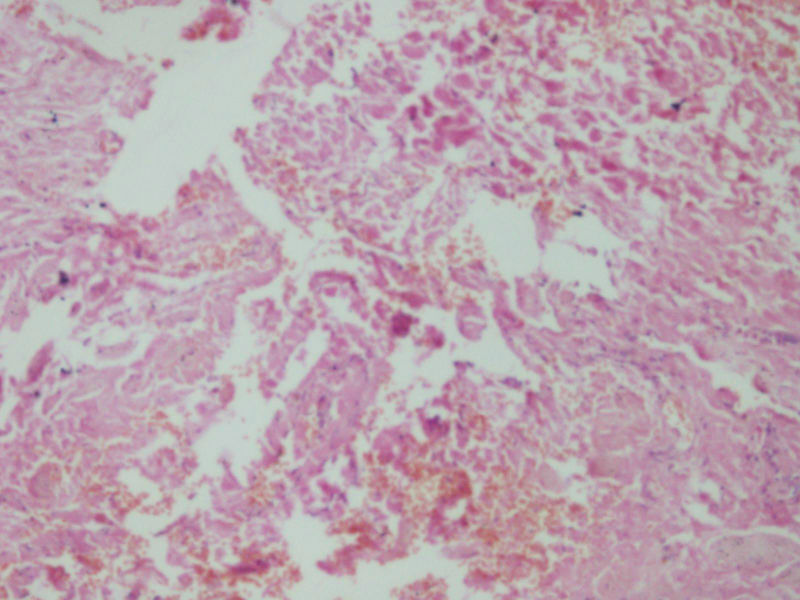

女17岁发现右大腿腘窝处一包块,渐进性增大4年,

• 右大腿包块图1

图1

肿物多大,有手术史吗?片子染得不太好,图三像异物。

据说肿物很大,但是送来只有黄豆大小,可能是只取了肿物周边的吧